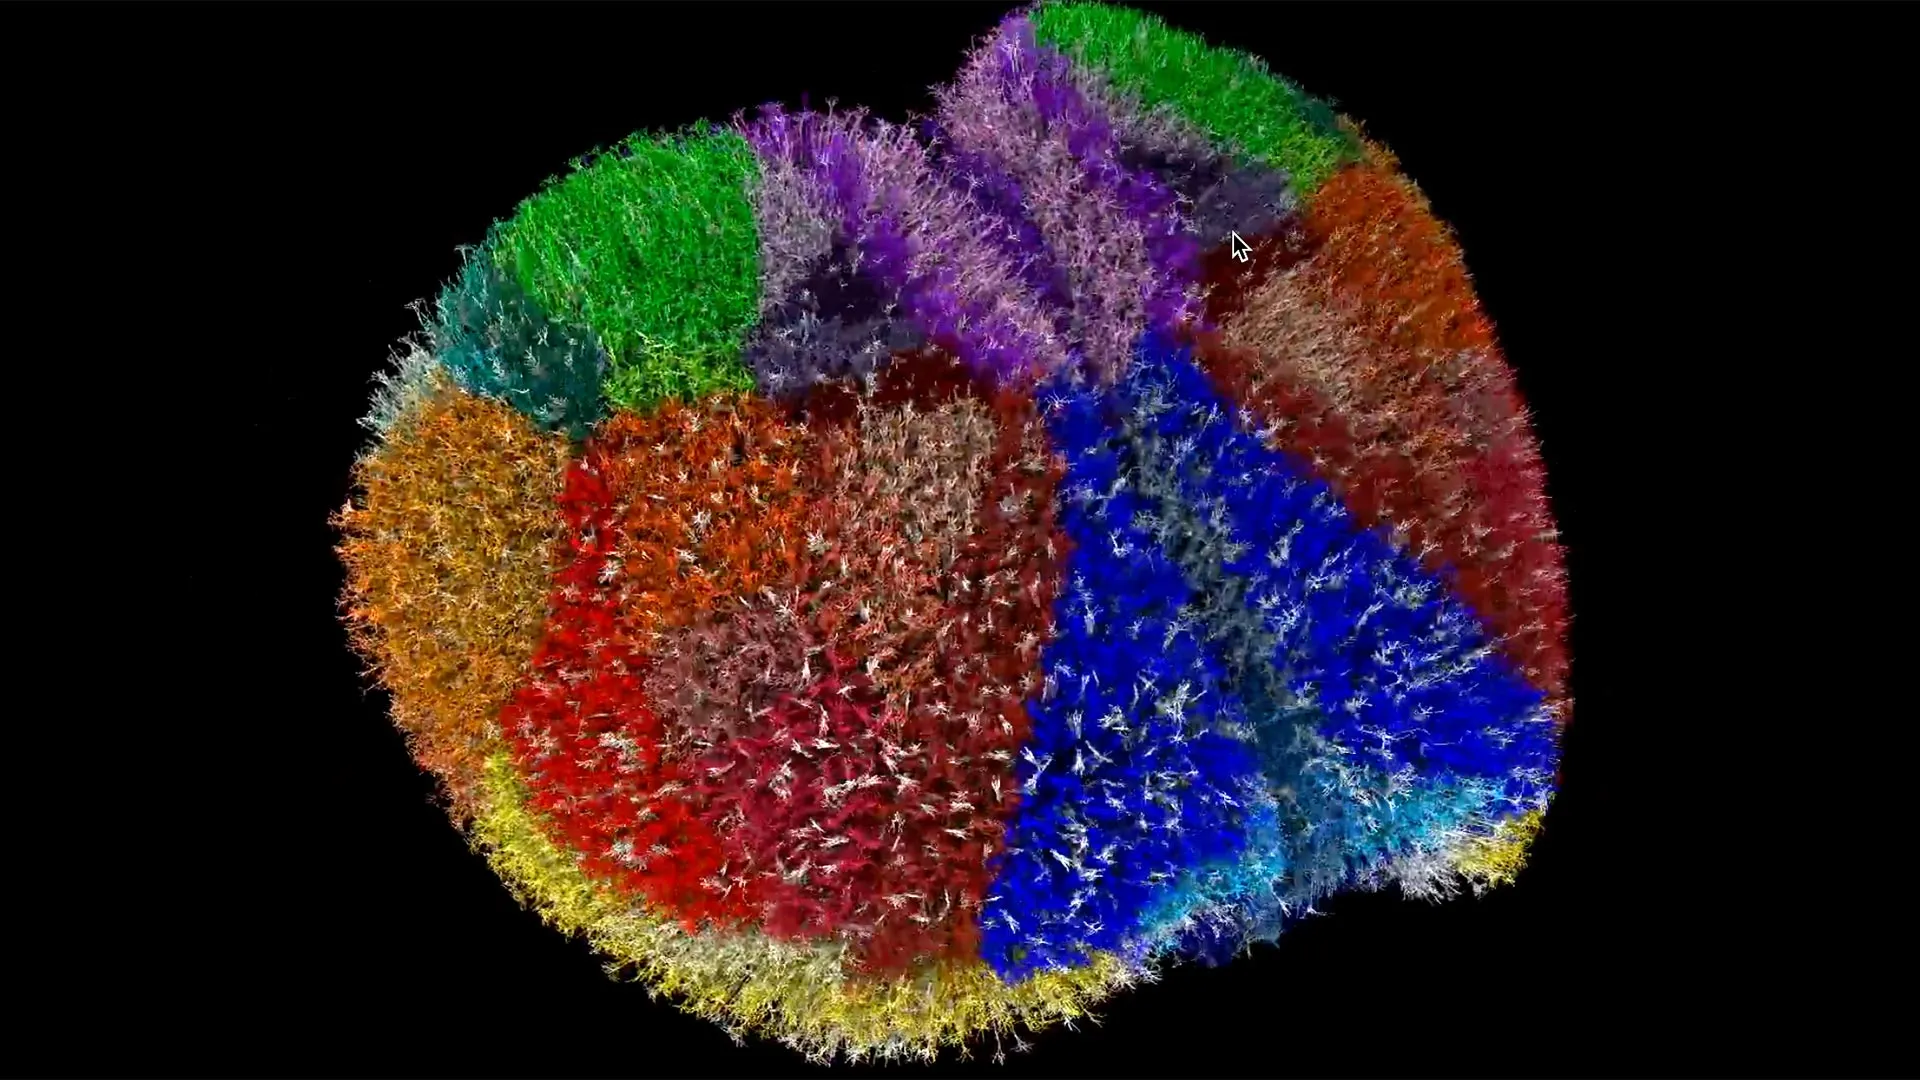

Οι νευρώνες είναι χρωματισμένοι ανάλογα με την περιοχή του φλοιού και φωτίζονται όταν είναι ενεργοί. Μόνο το 1% των νευρώνων εμφανίζεται για λόγους σαφήνειας. Η προσομοίωση αντιπροσωπεύει τη δραστηριότητα του φλοιού σε κατάσταση ηρεμίας.

Χρησιμοποιώντας το Brain Modeling ToolKit του Allen Institute, η ομάδα μετέτρεψε βιολογικά δεδομένα σε μία λειτουργική ψηφιακή ανακατασκευή του φλοιού. Για να προσομοιωθεί η ζωντανή συμπεριφορά των νευρώνων, ένα εργαλείο που ονομάζεται Neulite μετέτρεψε μαθηματικές εξισώσεις σε εικονικούς νευρώνες ικανούς να πυροδοτούν σήματα και να επικοινωνούν όπως οι πραγματικοί νευρώνες.

Η παρακολούθηση της προσομοίωσης μοιάζει με την παρατήρηση ζωντανής εγκεφαλικής δραστηριότητας. Το μοντέλο αναπαράγει λεπτομέρειες της δομής των νευρώνων, της δραστηριότητας των συνάψεων και της ηλεκτρικής σηματοδότησης μέσω των κυτταρικών μεμβρανών. «Είναι ένα τεχνικό επίτευγμα, αλλά είναι μόνο το πρώτο βήμα», δήλωσε ο Yamazaki. «Ο Θεός κρύβεται στις λεπτομέρειες, και γι’ αυτό πιστεύω στα βιοφυσικά λεπτομερή μοντέλα».